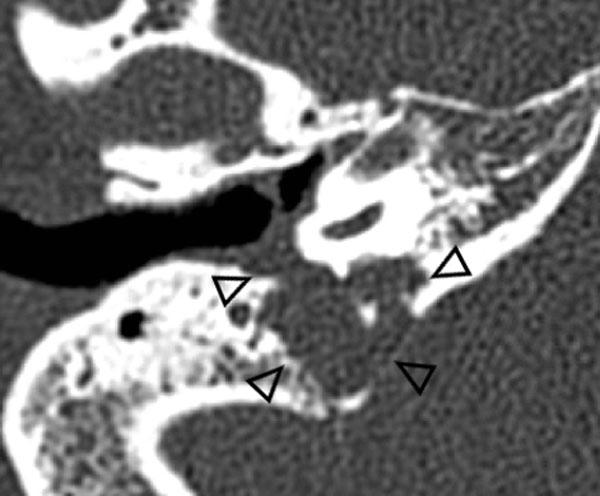

Đường đi bất thường của động mạch cảnh trong (ICA) hoặc động mạch bàn đạp

Đường đi bất thường của động mạch cảnh trong và sự tồn tại dai dẳng của động mạch bàn đạp là các biến thể bẩm sinh cần được nhận biết trên các phương tiện chẩn đoán hình ảnh.

Đường đi bất thường của động mạch cảnh trong tai giữa có thể bắt chước hình ảnh khối mô mềm hoặc u cận hạch khi soi tai.

Bên trái là hình ảnh đường đi bất thường của động mạch cảnh trong (mũi tên) và sự tồn tại dai dẳng của động mạch bàn đạp (đầu mũi tên) trên CT lát mỏng.

Lưu ý sự vắng mặt của lỗ gai (encircled).